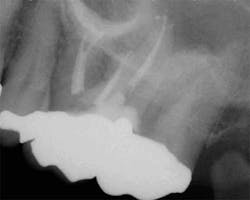

While mandibular incisors are my least favorite teeth to treat, the premolar teeth also provide significant reason for concern as they have highly variable anatomy. The maxillary first and second premolars will have one, two, or three roots and canals. (Figure 3) Maxillary premolar teeth have the smallest mean apical dimension at the apex (11) and the most variable anatomy, with exception of third molars. (12,17) The roots are often very thin, and a bulbous clinical crown may have significant taper to a thin root in the mesial-distal dimension that is broad in the facial-lingual dimension. It is not uncommon to see mesial-distal fractures in maxillary first or second premolars. Maxillary second premolars may have more curvature in the apical portion of the root when the sinus is close to the root ends. (Figure 4)

increased concern about the anatomy in tooth No. 5. This tooth

was subsequently retreated due to persistent symptoms.